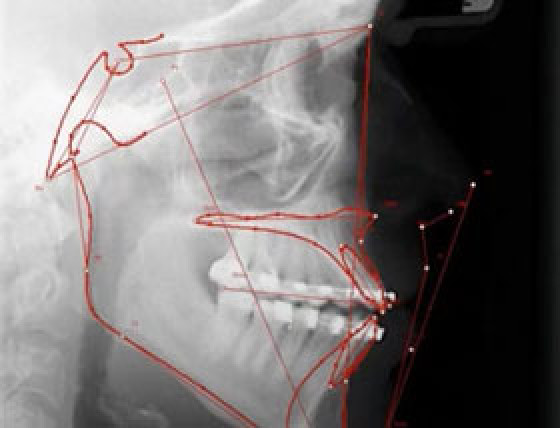

Mehr Klarheit in der Diagnostik mit ivoris® analyze

Ob Röntgen-, Foto- oder 3D-Aufnahmen – die Auswertung erfolgt direkt aus der Patientenakte. Vielfältige Darstellungsmodi erleichtern die Befundung und machen Ihre Ergebnisse auch für Patienten anschaulich. Über 100 Analysevorlagen geben Ihnen die Sicherheit, immer die passende Grundlage für Ihre Behandlungsplanung zu nutzen.

„Ich arbeite seit ca. 13 Jahren mit ivoris® analyze gekoppelt an meine Praxisverwaltungssoftware power.dent und eine individuelle Kieferorthopädieverwaltungssoftware. Für mich zählen Basisfunktionen und Anpassungsfähigkeit an meine Arbeitsumgebung. ‚Länderspezifische‘ oder ‚universitätsspezifische‘ Analysen sind in vielfältigster Art vordefiniert und an die persönlichen Bedürfnisse selbst oder unter Anleitung adaptierbar.“

Dr. Ernst Michael Reicher | Rudersdorf, Österreich, Kieferorthopädie für Kinder und Erwachsene